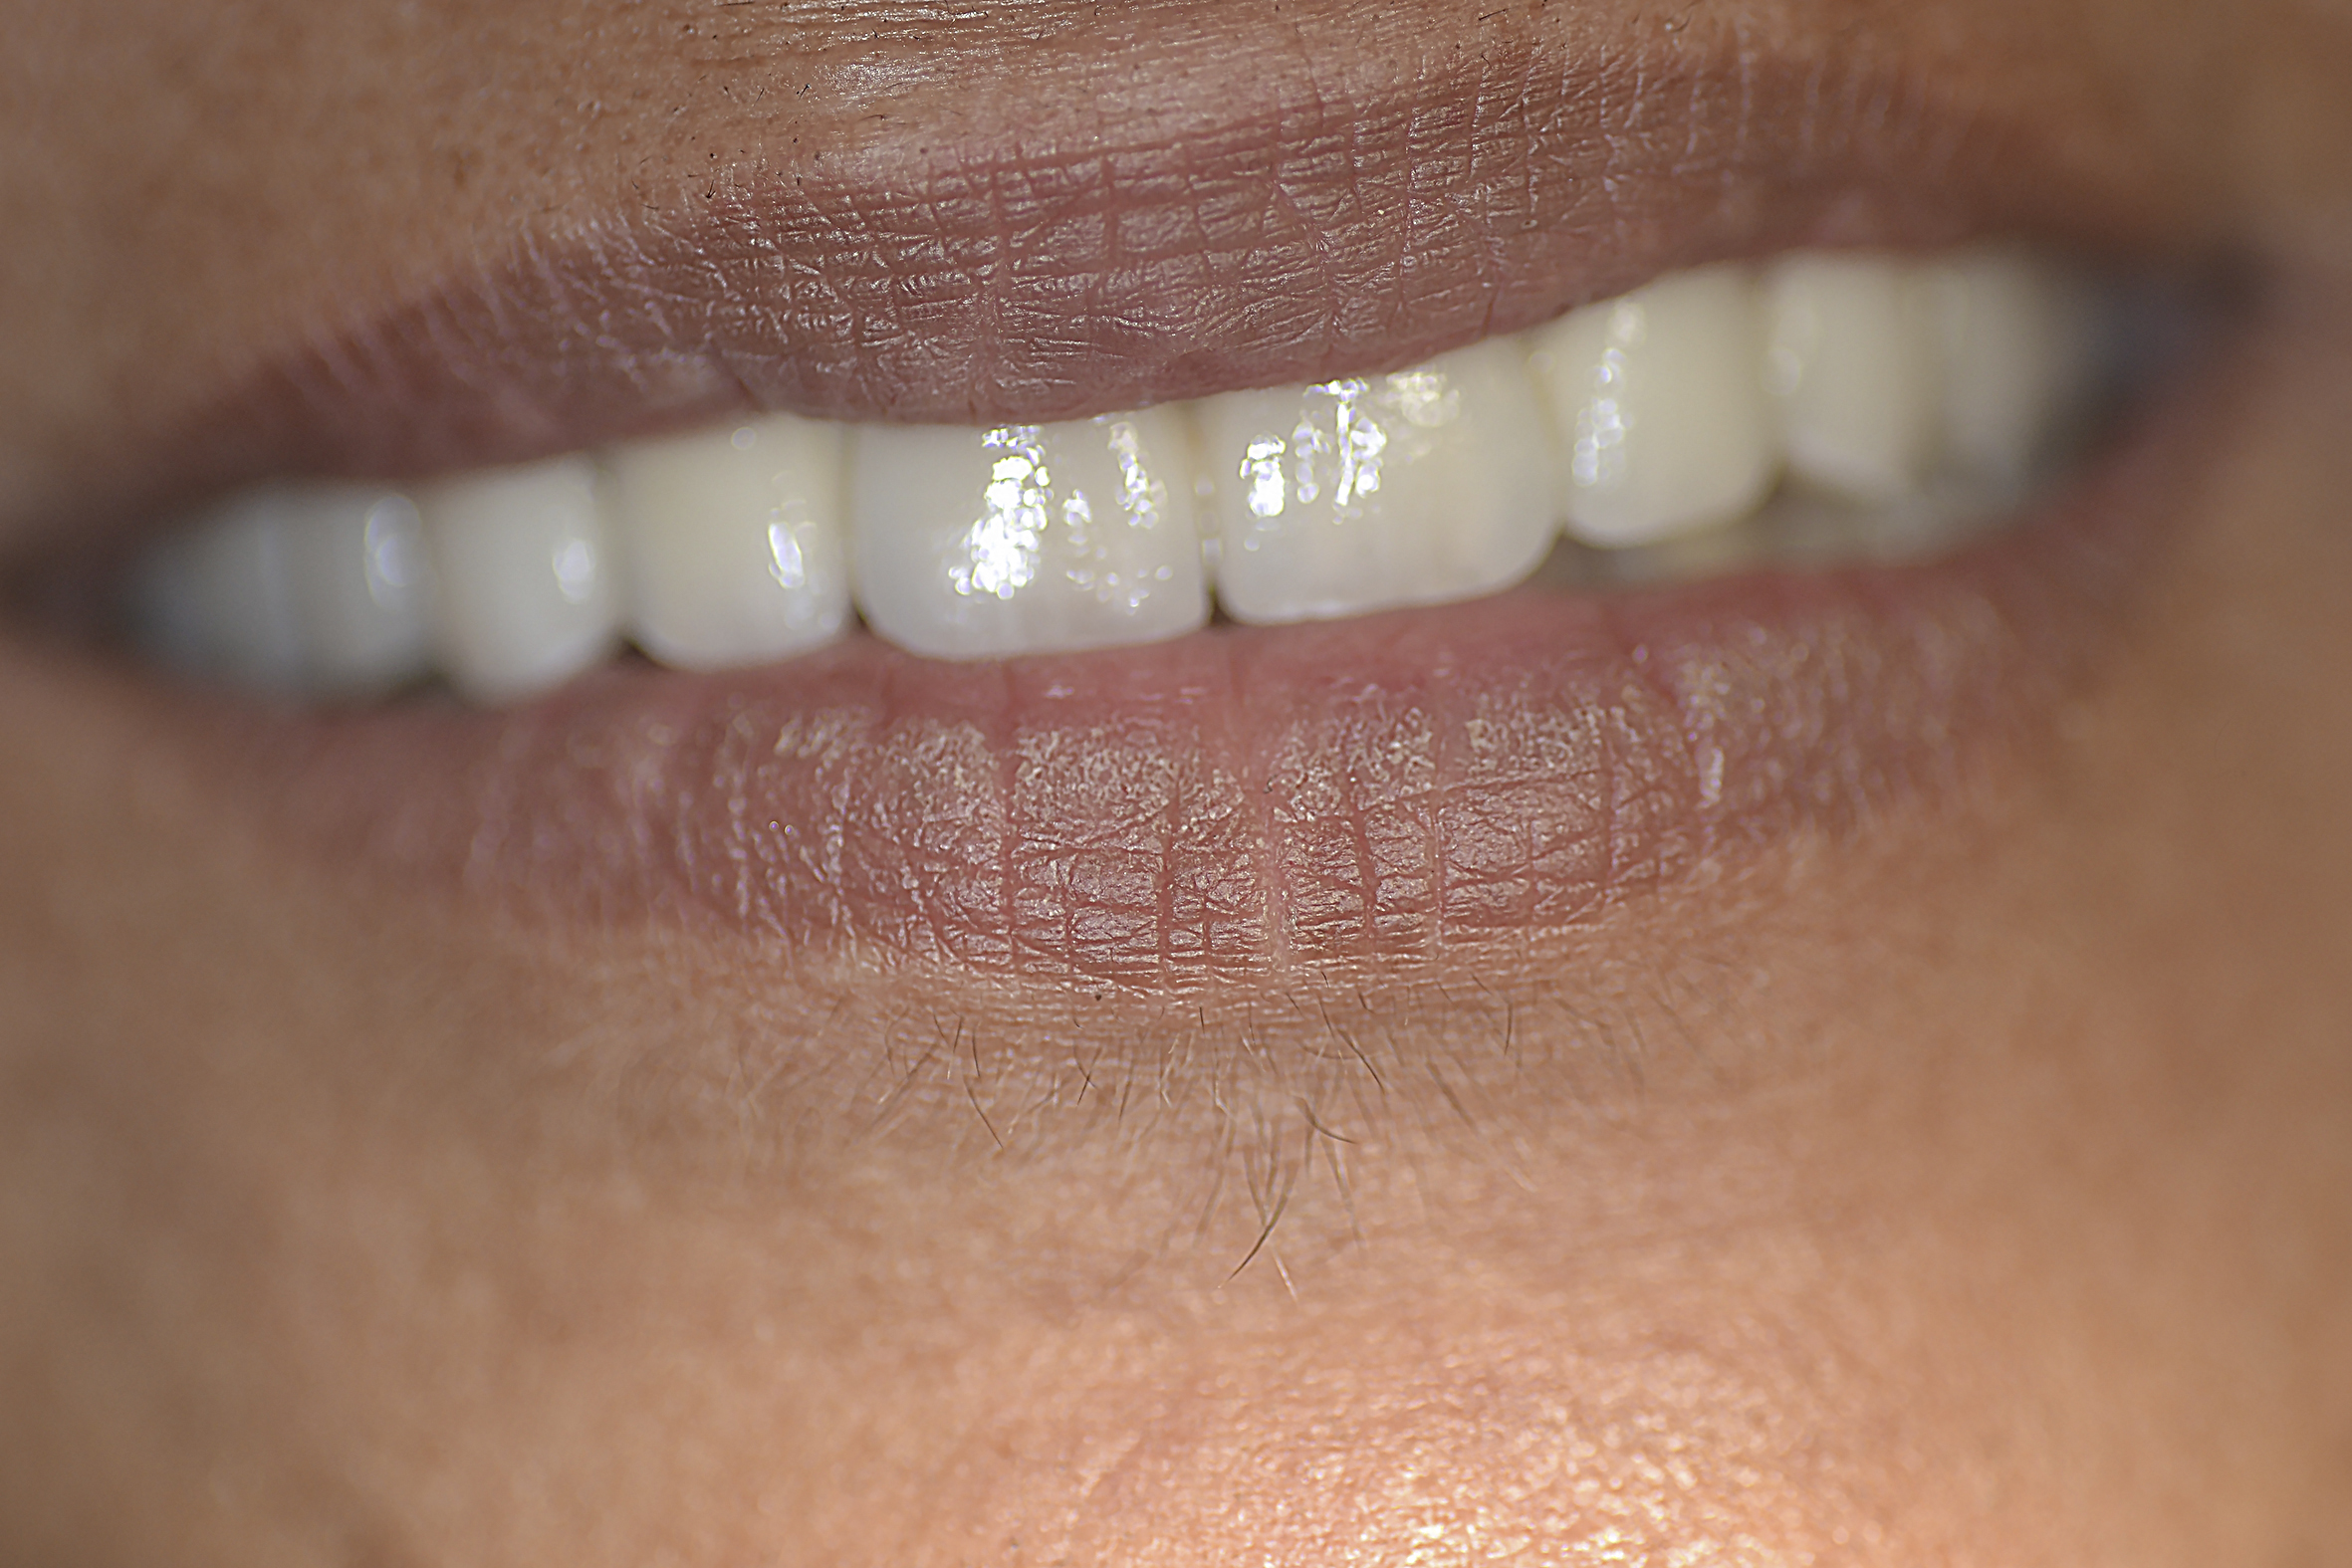

As a follow-up, the patient was guided to a strict oral hygiene and periodontal dental hygienist treatment regimen (Figure 5).

Fig 5. The completed treatments at 6-month follow-up.

Figure 5